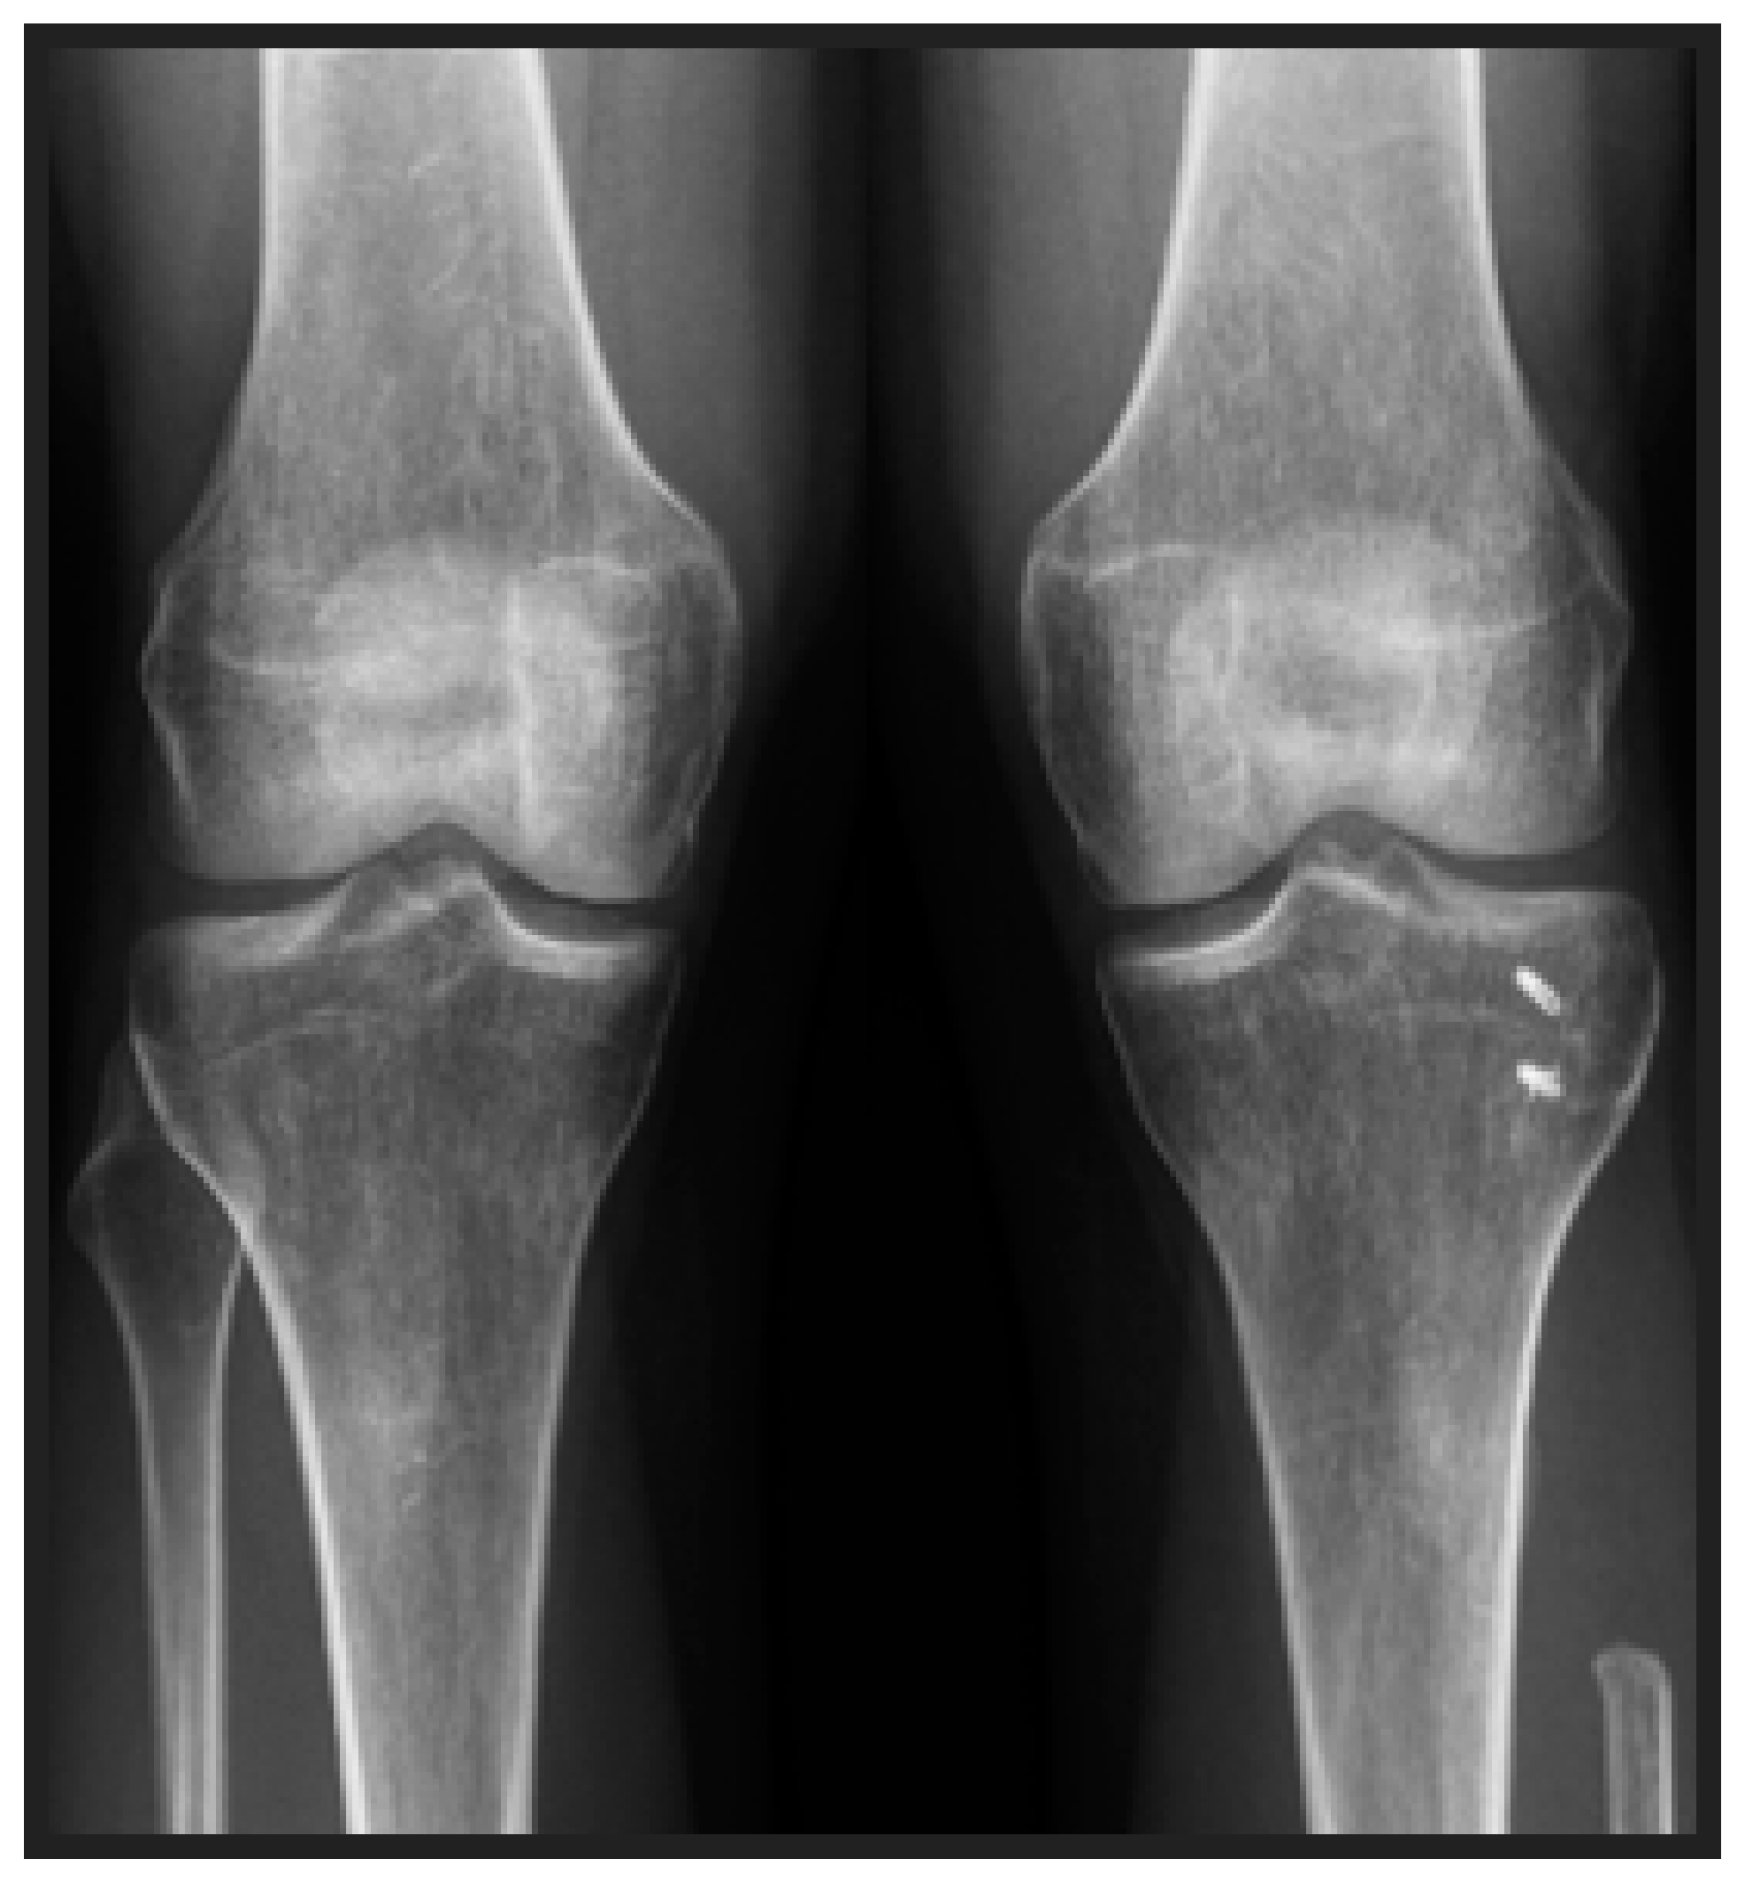

Proximal Fibula Resection for Tumors—Case Series and Technical Note

2. Methods